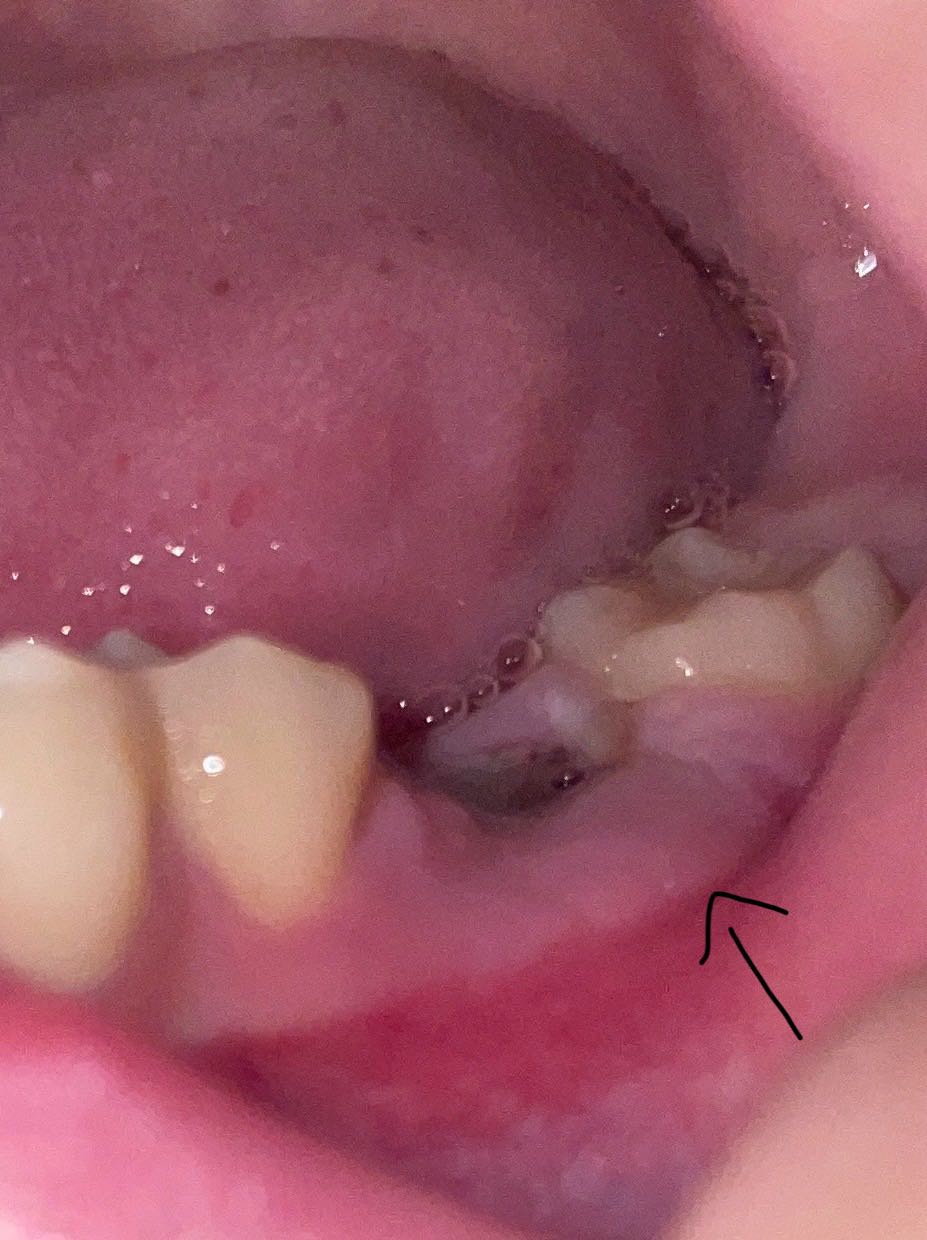

เหงือกบวมจากการถอนฟันกี่วันหายหรอคะ

ไปถอนมาจะเข้าวันที่3 เหงือกจะค่อยๆยุบเองมั้ยคะ หรือต้องกินยาคะ มีอาการปวดร่วมด้วยค่ะแต่ไม่ได้ปวดรุนเเรง ปวดๆหายๆ ขอบคุณสำหรับคำตอบล่วงหน้านะคะ🙇🏻♀️🩷

รูปภาพประกอบค่ะ